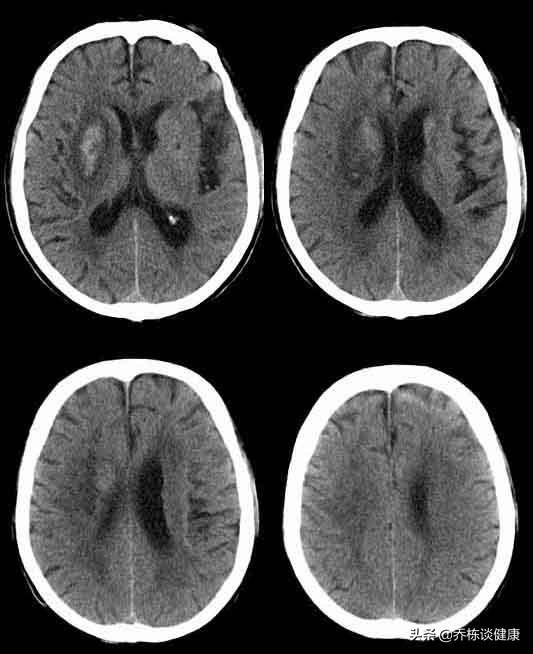

Les vertiges sont une manifestation clinique courante d'une variété de maladies. Après les symptômes de vertiges, il faut se rendre à l'hôpital pour procéder à un examen détaillé afin d'exclure les maladies organiques. Par exemple, des tumeurs intracrâniennes, des lésions professionnelles dans le canal rachidien cervical, etc. Le scanner cérébral et la pression artérielle ne posent pas de problème, ce qui indique qu'il n'y a pas de lésion intracrânienne et exclut les facteurs de causalité que sont l'hypertension ou l'hypotension artérielle.

Vertiges, une tension artérielle normale a été prise pour exclure les problèmes d'hypotension et d'hypertension, bien que la probabilité que ces types de problèmes causent des vertiges soit faible, et un scanner normal du cerveau indique que l'on peut exclure une pathologie intracrânienne, de sorte qu'au moins les problèmes dus au risque d'une maladie grave peuvent être réduits sans tarder.

Dans votre cas, la tension artérielle est normale et le scanner crânien est normal. Nous pouvons donc exclure les vertiges dus à la tension artérielle et les lésions cérébrales importantes. Il vous faut alors trouver la cause à partir des quatre aspects suivants.

La diminution de l'apport sanguin au cerveau, qui provoque des vertiges, est généralement due à une sténose des vaisseaux sanguins, qui ne peut être détectée par un scanner crânien ordinaire et qui peut être clarifiée par une échographie vasculaire cervicale et une échographie Doppler vasculaire intracrânienne.